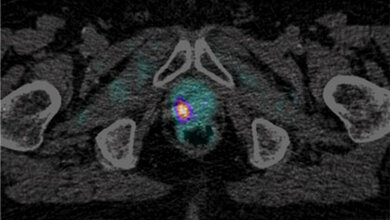

Forschende der ETH Zürich, des Universitätsspitals Zürich und der Universität Münster entwickelten erstmals eine Markersubstanz, dank der sich sogenannte NMDA-Rezeptoren auf der Oberfläche von Nervenzellen mittels Positronen-Emissions-Tomographie (PET) sichtbar machen lassen. NMDA-Rezeptoren sind vielsprechende pharmazeutische Zielstrukturen zur Therapie von verschiedenen neurologischen Krankheiten wie Alzheimer, Parkinson, Multiple Sklerose, Schizophrenie und Depressionen.

Die neue Markersubstanz – in der Fachsprache PET-Tracer genannt – soll bei der Erforschung solcher Krankheiten helfen. Bisher wurde die Substanz erst im Labor bei Ratten getestet. Dereinst möchten die Forscher damit aber Aktivitätsunterschiede zwischen Gehirnen von erkrankten und gesunden Menschen aufdecken und Therapiemöglichkeiten erforschen. Dies berichten die Wissenschaftler unter der Leitung von ETH-Professor Simon Ametamey im Journal of Nuclear Medicine. Insbesondere könnte der PET-Tracer helfen, die richtige Dosierung von zukünftigen Medikamenten zu finden, welche die Aktivität von NMDA-Rezeptoren beeinflussen. (idw, ETH, SNMMI)